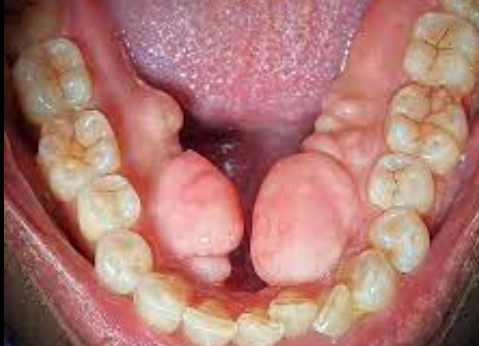

Torus

El torus palatino es una protuberancia ósea benigna que se desarrolla en el paladar duro de la boca. Es bastante común y generalmente no causa problemas, aunque en algunos casos puede interferir con el habla o la alimentación.

Apariencia:

Es una protuberancia, a menudo con forma ovalada o alargada, que puede variar en tamaño.